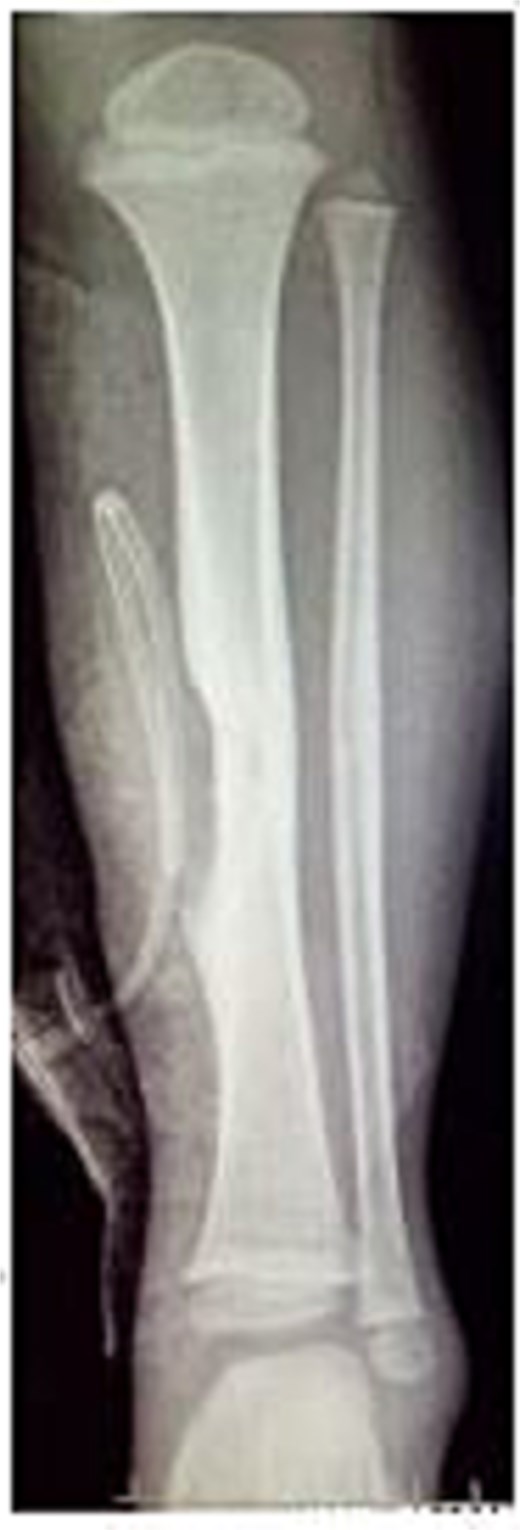

A 4-year-old boy presented with swelling on the medial aspect of his left leg. Three months prior, the patient had sustained a left tibial shaft fracture, initially treated conservatively. The swelling developed gradually with localized tenderness. On examination, the swelling was firm and tender to palpation, with intact overlying skin (Fig. 1). Radiography revealed erosion of the tibia (Fig. 2). Given the patient's fracture history, the initial differential included osteomyelitis, and empirical antibiotics were started. The vascular surgery team suspected a pseudoaneurysm and recommended further evaluation. Doppler ultrasound confirmed a pseudoaneurysm, revealing an abnormal vascular structure with turbulent blood flow. To delineate the vascular anatomy and identify the pseudoaneurysm's origin, magnetic resonance angiography (MRA) was ordered. It demonstrated the pseudoaneurysm arising from an unnamed posterior tibial artery branch, likely injured during initial trauma. The aneurysmal sac was located near the fracture site, eroding the underlying tibial bone (Fig. 3). The pseudoaneurysm's size warranted surgical intervention. The patient underwent excision of the aneurysmal sac and vessel wall repair (Fig. 4). Under general anesthesia, the aneurysmal sac was dissected out (Fig. 5), and the posterior tibial artery wall was repaired with lateral sutures. Hemostasis was achieved, and the wound was closed in layers. The patient had an uneventful postoperative recovery.